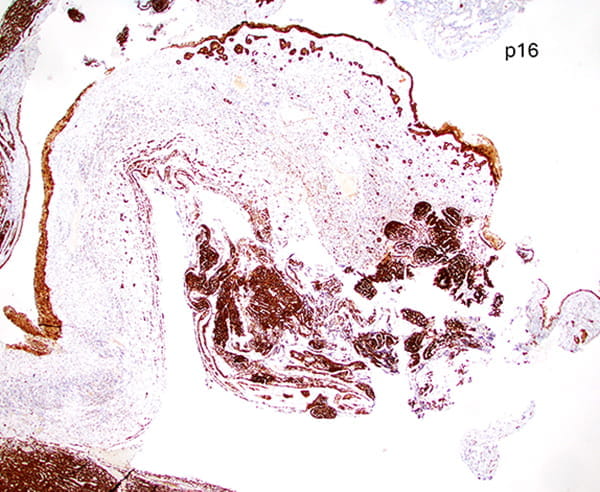

Immunohistochemical findings

Immunohistochemical staining for CK7 and p40 highlights dual cell populations, identifying ductal and myoepithelial components. P16 shows diffuse block positivity. High-risk HPV genotyping by PCR confirms the presence of HR-HPV types 33 or 58.